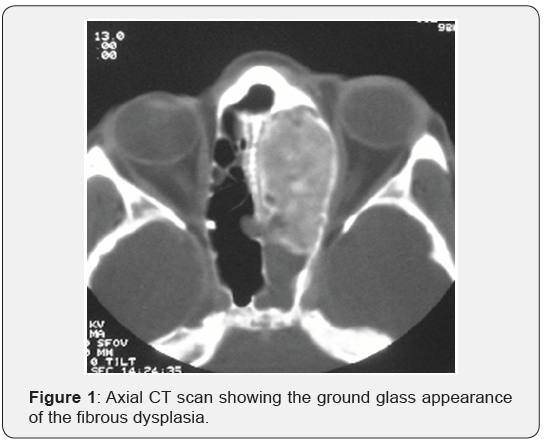

A 17 years old Saudi girl with a known case of FD which presented with a history of severe frontal headache for weeks and associated with dizziness. CT scan of paranasal sinuses was done and showed that almost total opacification of the nasal cavity, thickened septum and opacification of the frontal sinuses mainly right side. Middle cranial fossa showed ground glass opacity of the clivus and sphenoid bone as well as the nasal septum. The impression that was taken is FD. One month later, the patient presented to the ER with acute loss of vision on the right eye as well as syncope that lasted for 15-20 minutes. Following that she regained her consciousness completely as well as her vision on the right eye. A CT scan of paranasal sinuses was repeated and showed FD of anterior skull base including the sphenoid and ethmoid sinuses with narrowing of optic nerve canals bilaterally. From there, the patient was referred to the ENT service for further workup (Figure 1).

Fibrous dysplasia has monostatic and polystotic forms, depending on whether one or more bones are affected, which are noted in 30% and 70% of patients, respectively. Malignant transformation is rare and is usually seen only in polystotic cases. Following the ribs and long bones, craniofacial bones are the second most common site of involvement and comprise 25% of the cases. Among FD of the head and neck, the maxilla and mandible are the most frequent sites to be involved, followed by the frontal, parietal and occipital bones. However, FD of the paranasal sinuses is very rare. It is usually secondary to the extension of the disease from adjacent bones. Most commonly, FD is asymptomatic until there is encroachment upon adjacent vital structures. Atypical pain in the head and face as well as sinusitis symptoms are most frequent observed clinical findings [5]. The «ground glass» bone appearance on C-T scans with bone window is the most useful radiographic sign for the diagnosis of FD. Treatment is aimed at correcting or preventing functional problems and achieving normal facial aesthetics [6].